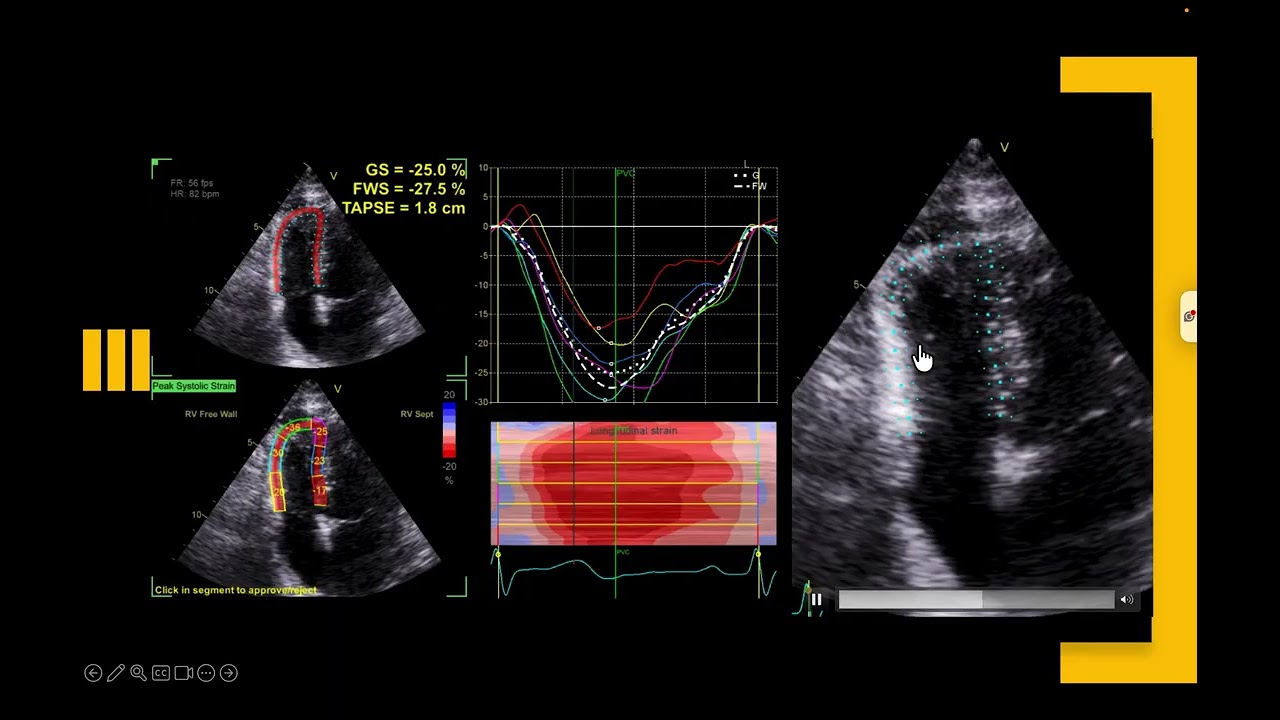

RV Strain Simplified: Views, ROI & Variability Explained. Why Your Numbers May Not Be Right🫀⚠️

Описание: Right Ventricular (RV) strain analysis is powerful—but only when done right 🫀📊

In this video, we walk through the practical steps and common pitfalls of RV strain assessment, starting with acquiring a true focused RV view and avoiding anterior or posterior angulation that can distort results.

We would discuss accurate endocardial border tracing, correct region of interest (ROI) selection, how to avoid free wall/surface artefacts, and why many labs use LV GLS software for RV strain. Finally, we address the high variability in RV strain values and how technique, software, and image quality influence interpretation—helping you generate reliable, clinically meaningful RV strain data 🎯🩺